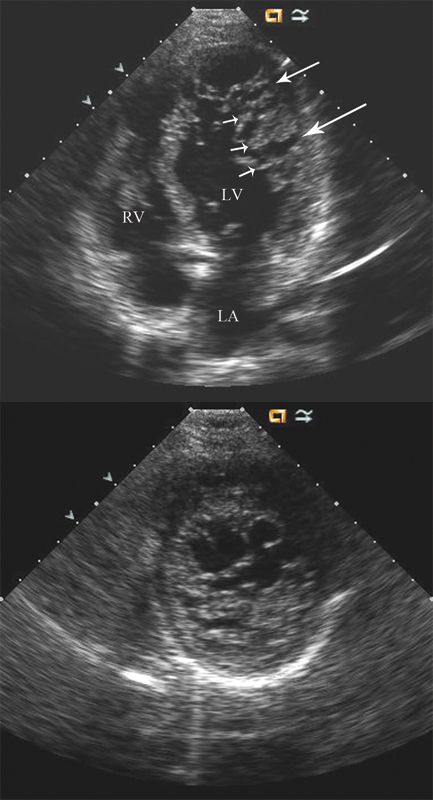

فحوصات تشخيصية لبعض امراض القلب والشرايين التاجية